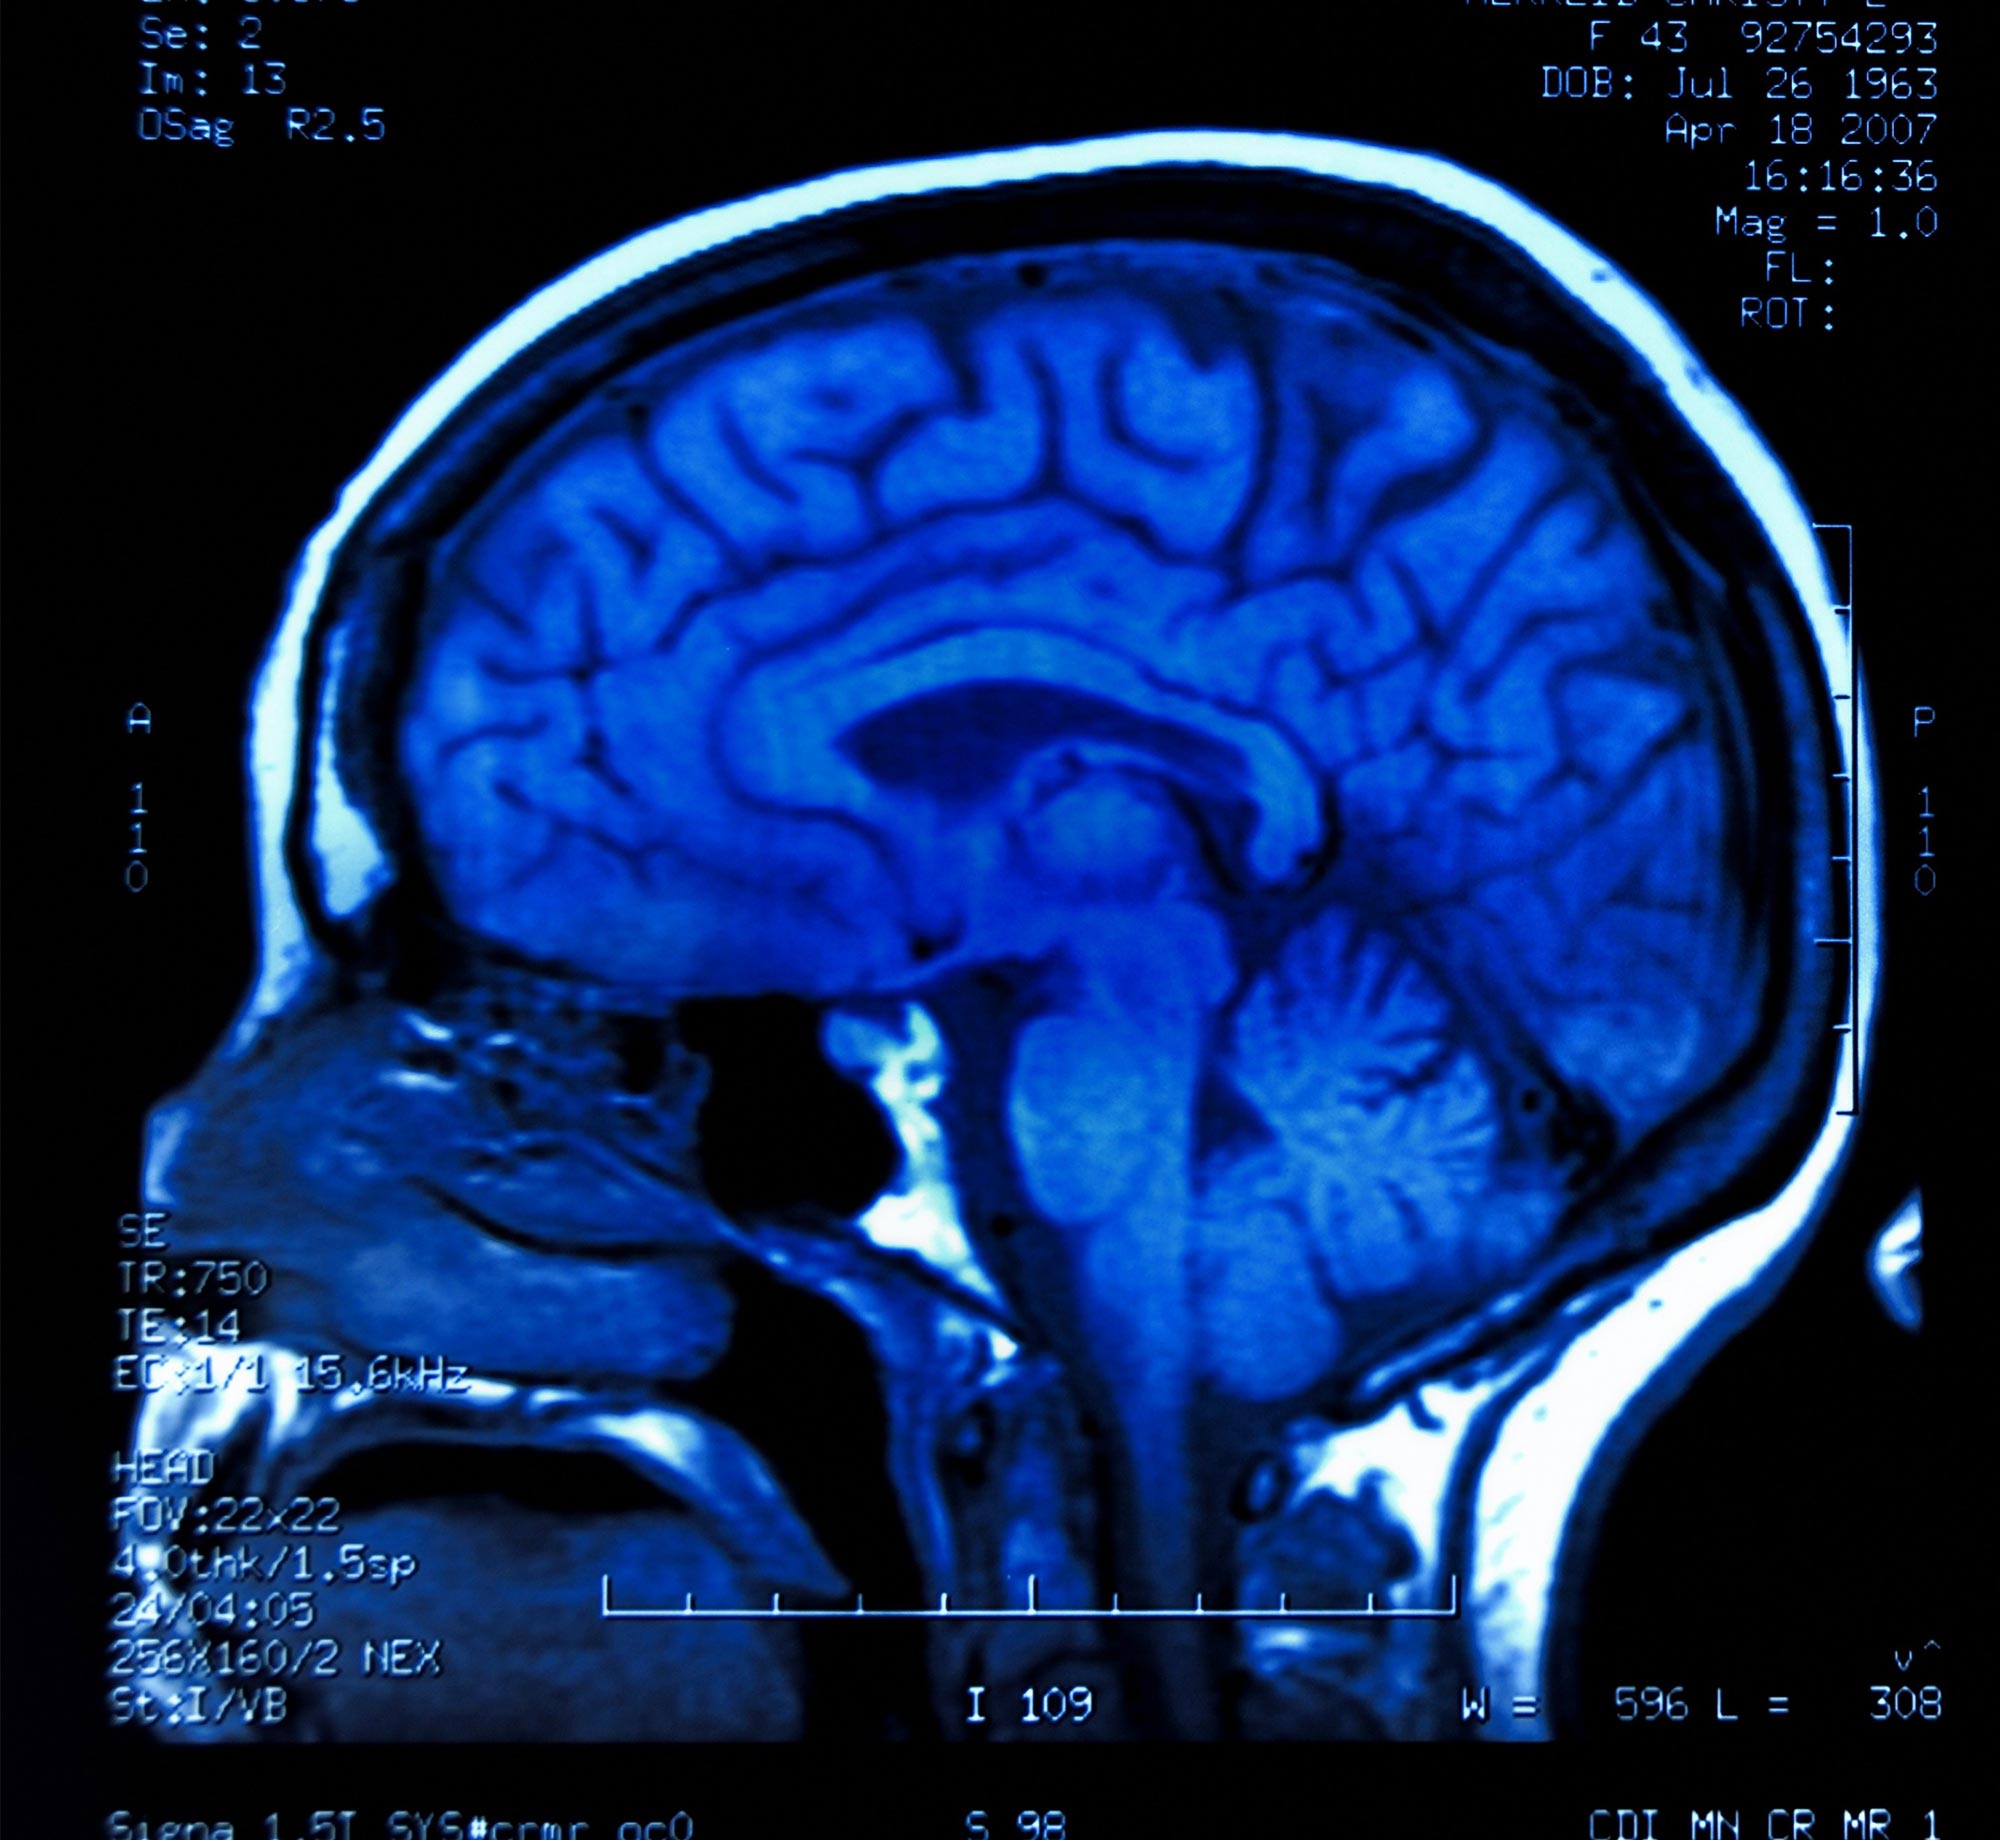

Research from Osaka Metropolitan University shows that while the Alzheimer's drug lecanemab reduces amyloid plaques, it does not improve the brain's waste clearance system in the short term, highlighting the disease's complexity and the need for multi-targeted therapies.